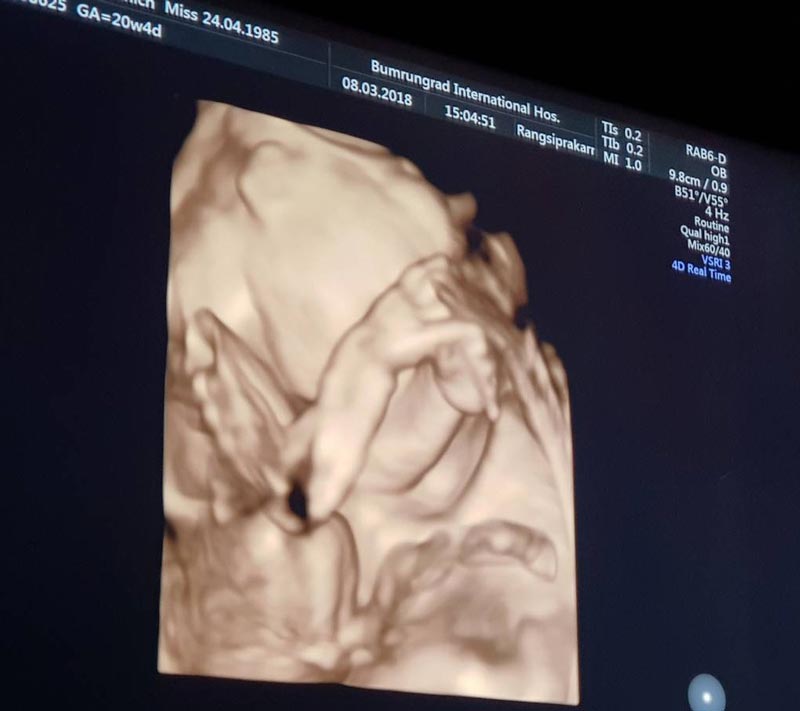

"ในที่สุดลูกชายแม่ก็มา ขอบคุณสวรรค์ที่มอบลาภอันประเสริฐมาให้ ดีใจที่สุดเลย #ฟินเวอร์ #น้ำตาคลอ แม่ซึ้งเห็นผู้ชายแล้วน้ำตาไหล ... เป็นเรื่องราวดี ๆ ที่เข้ามาอีกเรื่องในชีวิต ขอบคุณทุกๆคำอวยพรจากทุกๆคนนะคะ แม่ฟินมากกกกกกกพูดเลยยยย #20weekspregnant #welcomemyboy สามีพี่ยิ้มกว้างมากกกกก @por_tnp"